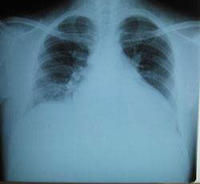

2.X線檢查:心影增大,心胸比>0.6,肺淤血征,有時伴胸腔積液。

2.胸部X線檢查心影多增大,但有些患者在心影增大之前左心室已明顯向後增大。由於胸片反映右心室擴大的敏感性要較左心室擴大為高,而右心衰竭常提示預後不良,所以胸片對預後判斷有一定意義。肺靜脈高壓時可有KerleyB線。有心包積液時透視下可見心臟搏動減弱。

2.心臟擴大 X線檢查心胸比>0.5,超聲心動圖示全心擴大,尤以左心室擴大為顯,左室舒張期末內徑≥2.7cm/m2,心臟可呈球型。